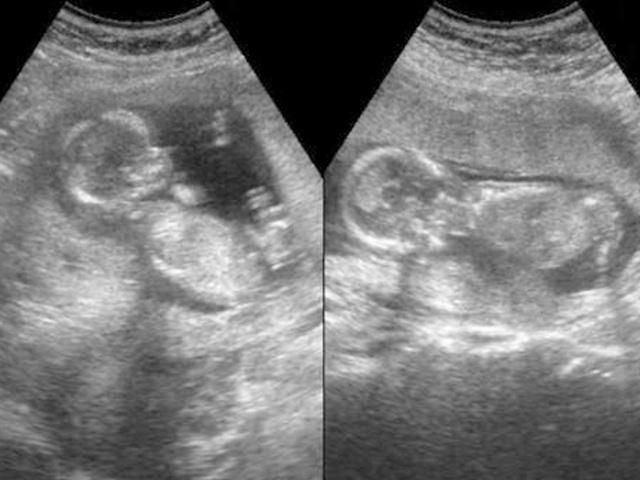

25岁准妈妈怀孕7个月引产,之后情绪崩溃

怀孕之后托人查验是儿子,心里就踏实多了,可是到了怀孕7个月的时候,再次查验被告知是女儿,当时她心都凉了。

引产结束,她瞄了一眼,看到已经成型、奄奄一息的胎儿,整个人瞬间崩溃,彻底沉默了。

引产是一个复杂的过程,简单来说就是需要先用一些特殊手段伤害胎儿,再使用一些特殊手段,像正常分娩那样,把胎儿分娩出来,只是分娩得到的是一个健康的宝宝,而引产的结果是一个奄奄一息或者是已经死亡的胎儿。